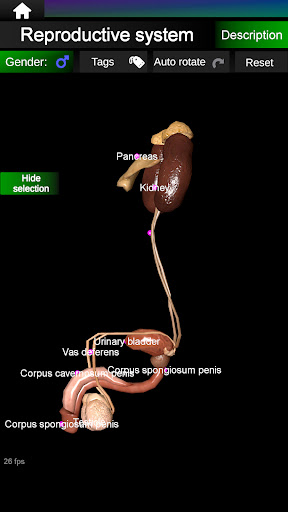

* Sistem reproduksi, yang meliputi organ reproduksi pria dan wanita.

* Bandingkan organ pria dan wanita.